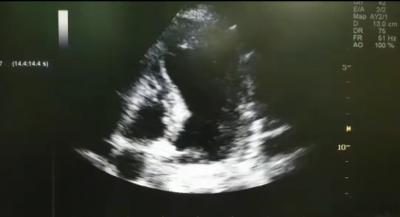

Ischemic Cardiomyopathy

Bedside echocardiogram showed dilated left ventricle (LV) on a apical 4-chamber view.